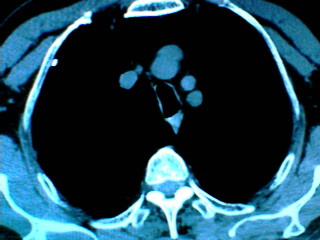

老年男性患者,右侧胸疼1月余(不是左侧),无其他症状

左肺外周类圆形病灶,其内低密度,可见液平及气影,周围肺文理见渗出样变,考虑左肺外周带肺脓肿。

支持肺囊肿,液体含量多,可能与支气管不通.右侧胸膜局限性肥厚,可能是导致痛的原因.

支持肺囊肿,右侧胸膜肥厚粘连钙化.